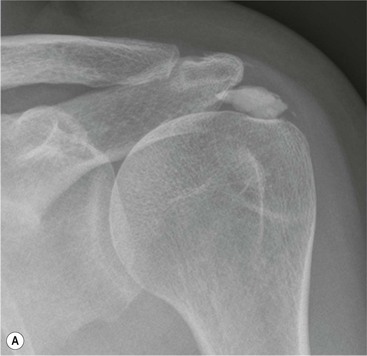

Radiography is useful for demonstrating bony abnormalities of the AC joint and acromion and excluding associated GHJ arthrosis (Fig. 46-1). Marked narrowing of the subacromial space is a specific but insensitive sign of a full thickness rotator cuff tear3 (Fig. 46-2). MRI and ultrasound (US) directly visualise the rotator cuff tendons. Both techniques are capable of diagnosing tendinopathy (Fig. 46-3), and have nearly 100% accuracy rates for FTTs of the rotator cuff.4 MR arthrography is not usually indicated for primary rotator cuff disease. The most important features to describe that help determine management include the following:

More severe injury may be associated with a bony injury of the glenoid rim, usually called a bony Bankart lesion (Fig. 46-10). Non-enhanced CT may occasionally be preferred to assess the size of the bony defect of the glenoid. There is usually associated impaction injury on the posterosuperior aspect of the humeral head called a Hill–Sachs defect (Figs. 46-11 and 46-12).